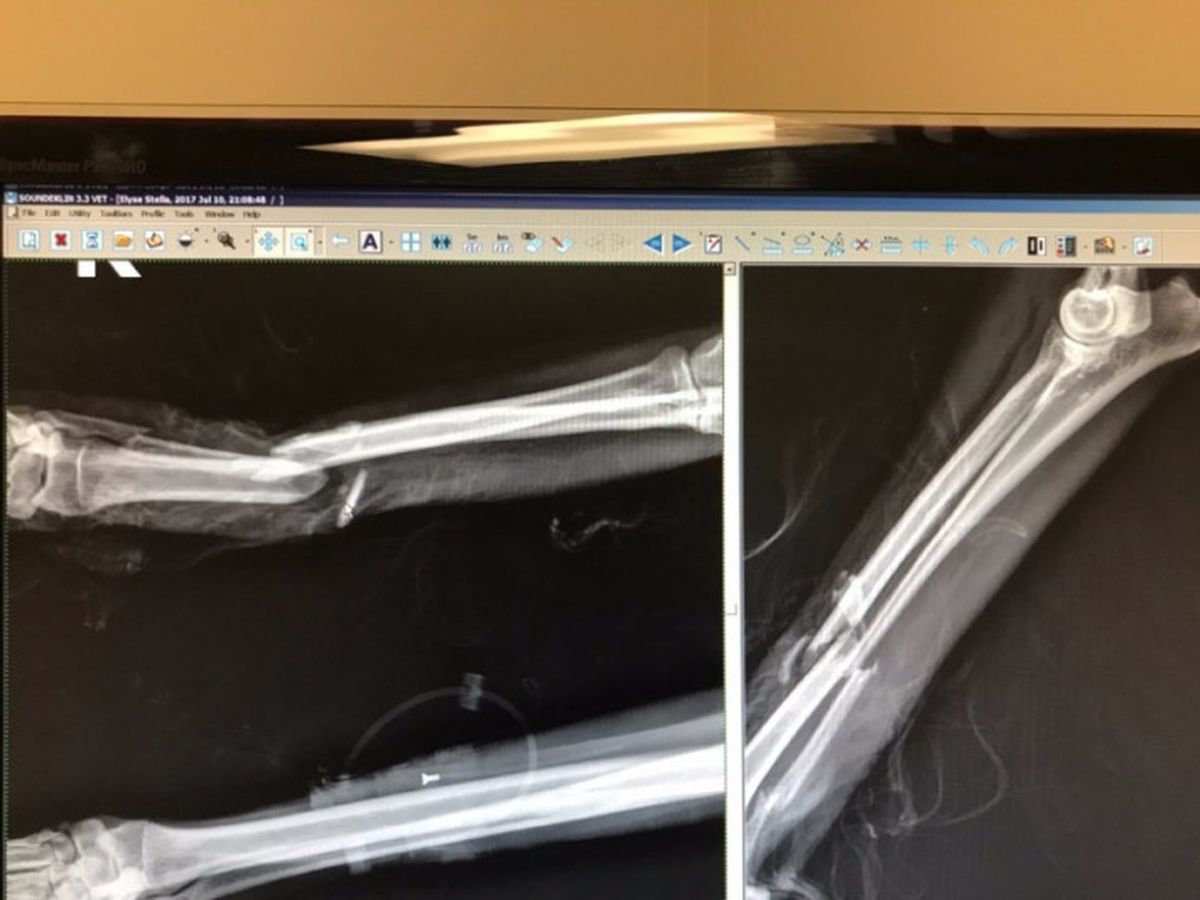

On a beautiful Monday evening, July 10th, my neighbors Elyse and Zach Smith were taking a pleasant stroll near The Castaways with their rescued Afghan Hound....STELLA. They were almost home when they came upon a man running with a Pit Bull. Elyse and Zach paused to let them run by however, once the Pit Bull had passed the Smith's, the Pit Bull turned around and began viciously attacking them with Stella taking the brunt of the attack. Zach made every attempt to intervene as he cuffed Stella's neck while they both attempted to push away the Pit Bull. Elyse and Zach suffered multiple bites to their arms, hands and legs and suffered dislocated and broken fingers... All the while....the man who was running with the dog DID NOTHING! Once the Smith's were able to separate the two dogs, the man and the Pit Bull ran off leaving them screaming for help and bleeding. A good Samaritan stopped to help, and they loaded Stella into their car and rushed her to the Emergency Vet. Stella underwent emergency surgery that evening. Stella's leg is shattered in three places and has severed tendons, muscles and arteries. This will be the first of many surgeries and urgent care for her.

Stella was rushed to the Central Orange County Emergency Vet on July 10th where she went into her first surgery. The next day she was transfered to Veterinary Specialist Services Orange County (VSSOC) where they stabilized her and Stella's vet Dr. Sebestyen performed a several hour long surgery reconstructing her leg with titanium plates, screws and bone putty fusion.